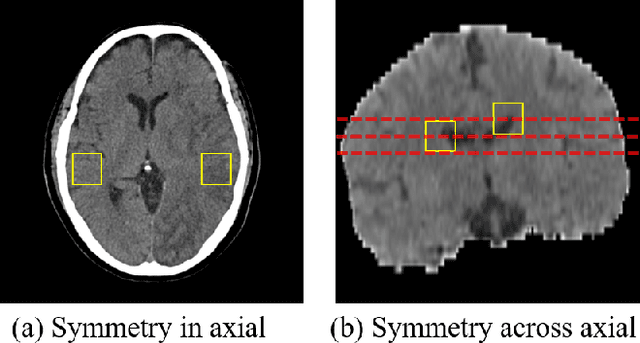

Quantitative estimation of the acute ischemic infarct is crucial to improve neurological outcomes of the patients with stroke symptoms. Since the density of lesions is subtle and can be confounded by normal physiologic changes, anatomical asymmetry provides useful information to differentiate the ischemic and healthy brain tissue. In this paper, we propose a symmetry enhanced attention network (SEAN) for acute ischemic infarct segmentation. Our proposed network automatically transforms an input CT image into the standard space where the brain tissue is bilaterally symmetric. The transformed image is further processed by a Ushape network integrated with the proposed symmetry enhanced attention for pixel-wise labelling. The symmetry enhanced attention can efficiently capture context information from the opposite side of the image by estimating long-range dependencies. Experimental results show that the proposed SEAN outperforms some symmetry-based state-of-the-art methods in terms of both dice coefficient and infarct localization.